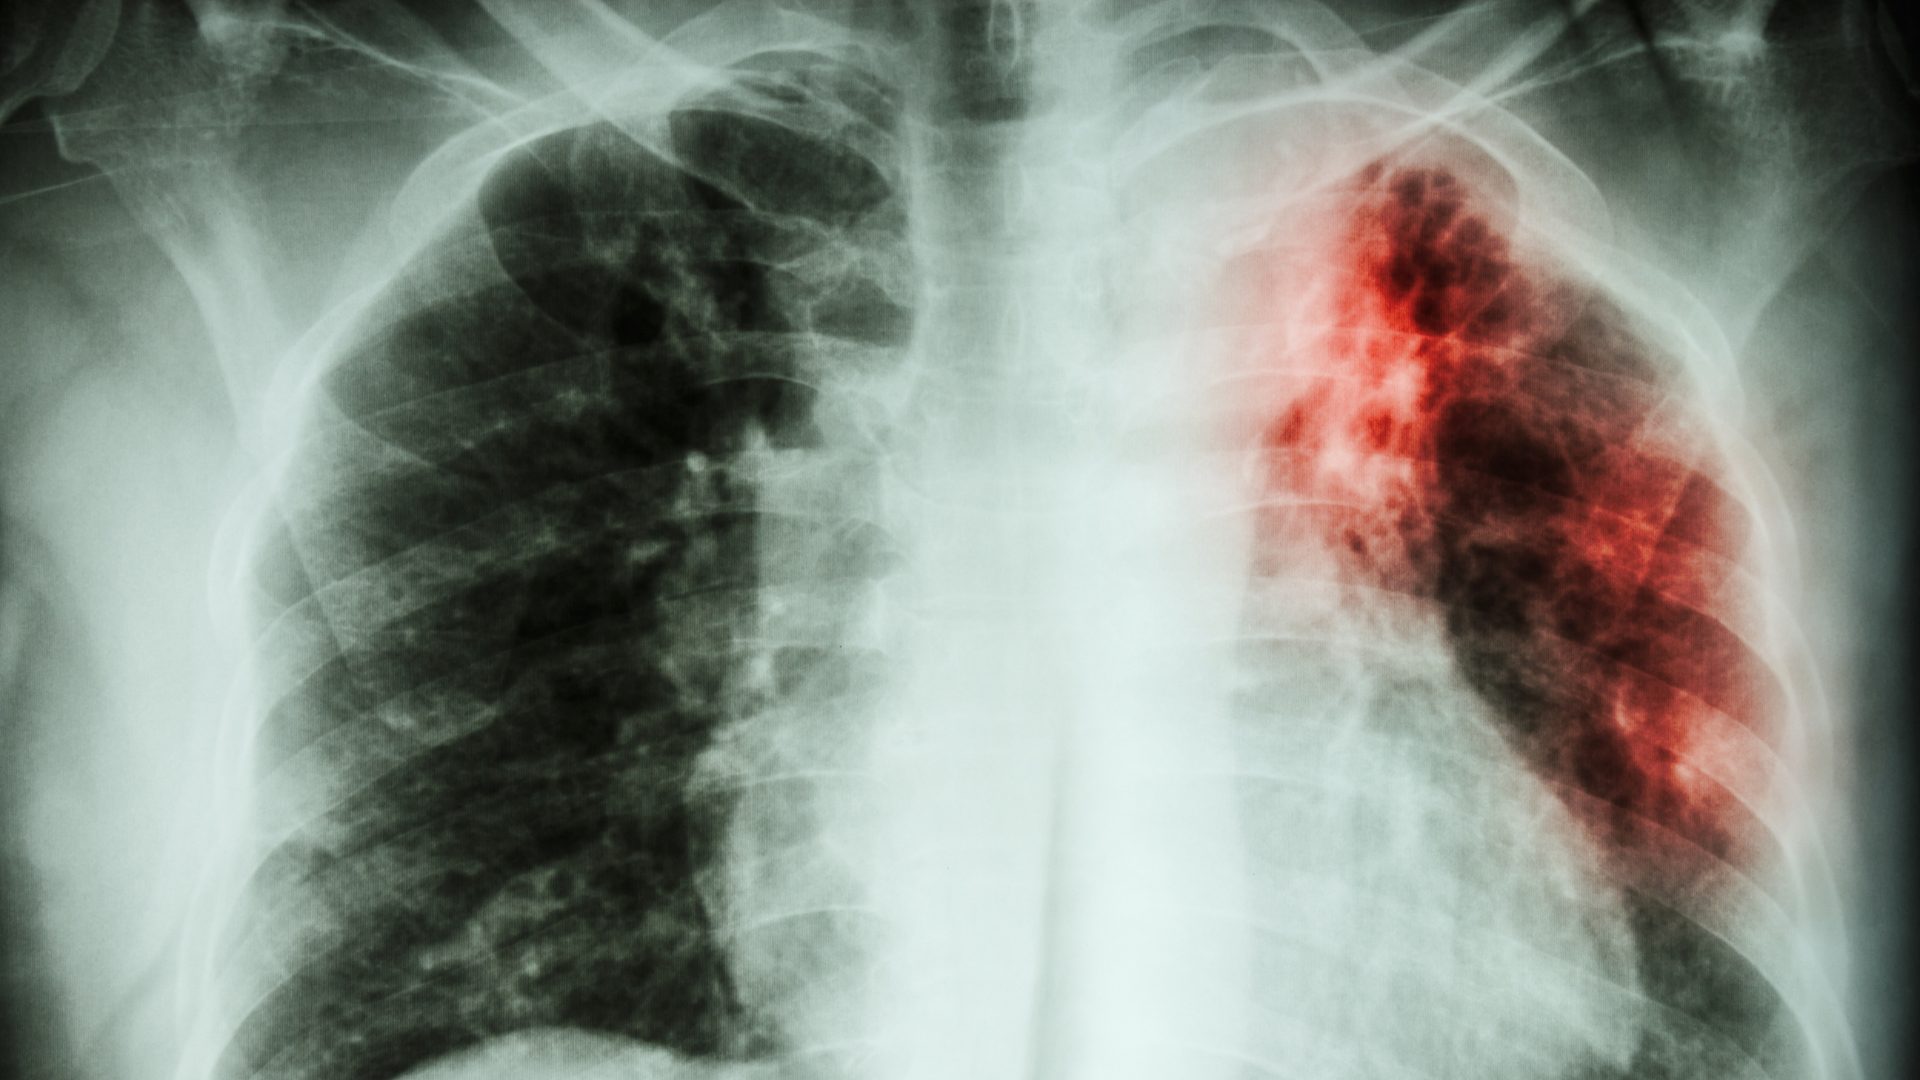

A Organização Mundial de Saúde estima que, no ano passado, um total de 105 mil brasileiros adoeceram por tuberculose dos quais 87.344 foram diagnosticados e tratados. Isso representa 83% de detecção de pessoas com a doença, percentual 9,5% maior do que em 2021, quando o resultado do país foi de 75,8%.

O Relatório Global de Tuberculose 2023 revelou que houve recuperação global no número de pessoas diagnosticadas e tratadas para tuberculose, após dois anos de interrupções relacionadas à pandemia de coronavírus. A tuberculose ainda é a segunda principal causa de morte no mundo devido a um único agente infeccioso em 2022, depois da Covid-19.

Outro fato demonstrado no relatório é que parte dos brasileiros não finalizam o tratamento para tuberculose, que tem duração mínima de seis meses e que pode se prolongar até 18 meses. Em 2021, apenas 65% das pessoas diagnosticadas no Brasil completaram o tratamento e foram curadas. No caso de pessoas vivendo com HIV ou aids, o percentual foi de 44%.